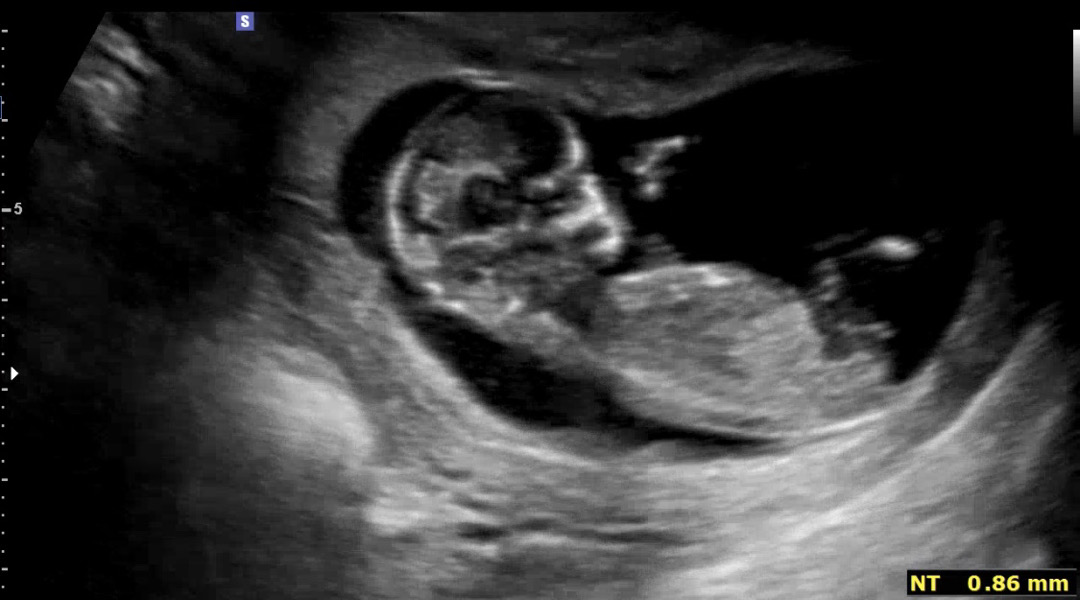

각도법 봐주실 분!!!

부탁드립니당 !!!